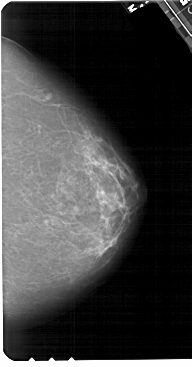

A_1552_1.RIGHT_CC

RIGHT_MLO LINES 5491 PIXELS_PER_LINE 3076 BITS_PER_PIXEL 12 RESOLUTION 43.5 NON_OVERLAY